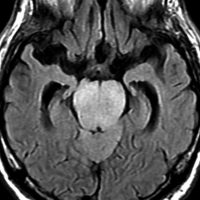

MRI画像所見 60代で嚥下障害と構音障害で発症した例

延髄から中脳まで腫瘍があって脳幹部が腫れています。この画像ですと,小児のびまん性橋膠腫(DIPG,びまん性正中グリオーマ)のように見えます

両側視床から大脳基底核,両側大脳半球深部白質,脳梁まで広範囲に腫瘍が存在します。退形成性星細胞腫のようにまだらにガドリニウム増強されます。